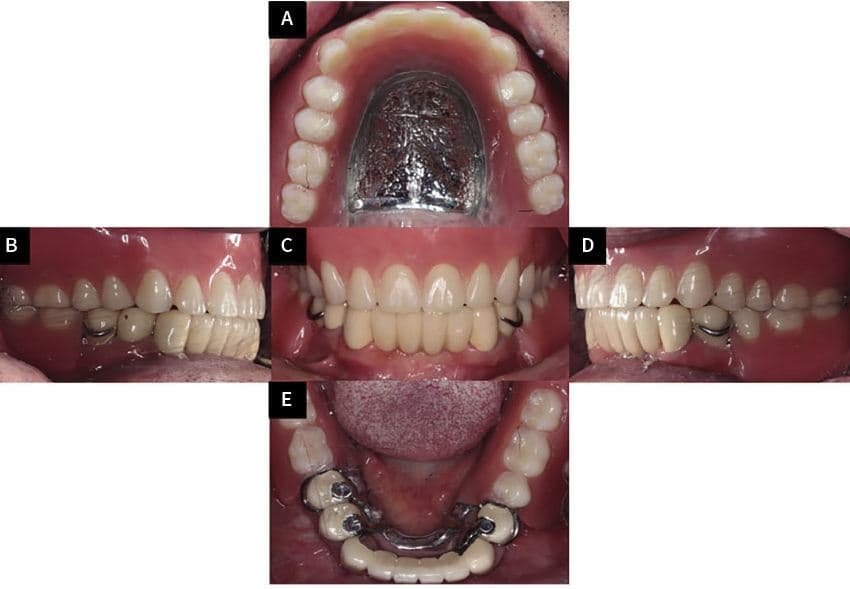

Yonsei universiteti stomatologiya fakulteti talabalari klinik mashg'uloti

89-Koreya stomatologiya protez jamiyati ilmiy anjumani ma'ruzasi

Talaba klinik yo'riqnomasi (Dr. Kim Yu-seong)

Talaba klinik yo'riqnomasi (Dr. Kim Jin-hyeong)

89-Koreya Stomatologik Protezlash Jamiyati ilmiy konferensiyasi taqdimoti